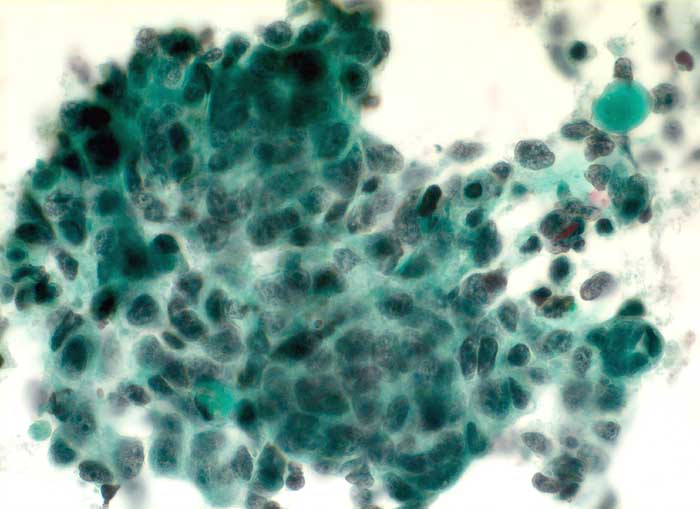

Plattenepithelkarzinom: Hirnmetastase

Schnellschnittflüssigkeit Hirn frontal rechts: hochgradig atypische Epithelien bilden einen grösseren Verband. Die Kerne sind deutlich vergrössert, hyperchromatisch und stark polymorph. Das Chromatin ist grob gekörnt, die Kerne ähneln teilweise Lavabrocken. Pro Kern erkennt man 1-2 vergrösserte Nukleolen. Das Zytoplasma ist teils schmal und uncharakteristisch, gelegentlich polygonal.

Zytologische Diagnose: Schnellschnittflüssigkeit Gehirn: Zahlreiche Karzinomzellen. Befund vereinbar mit Metastase eines Plattenepithelkarzinoms.